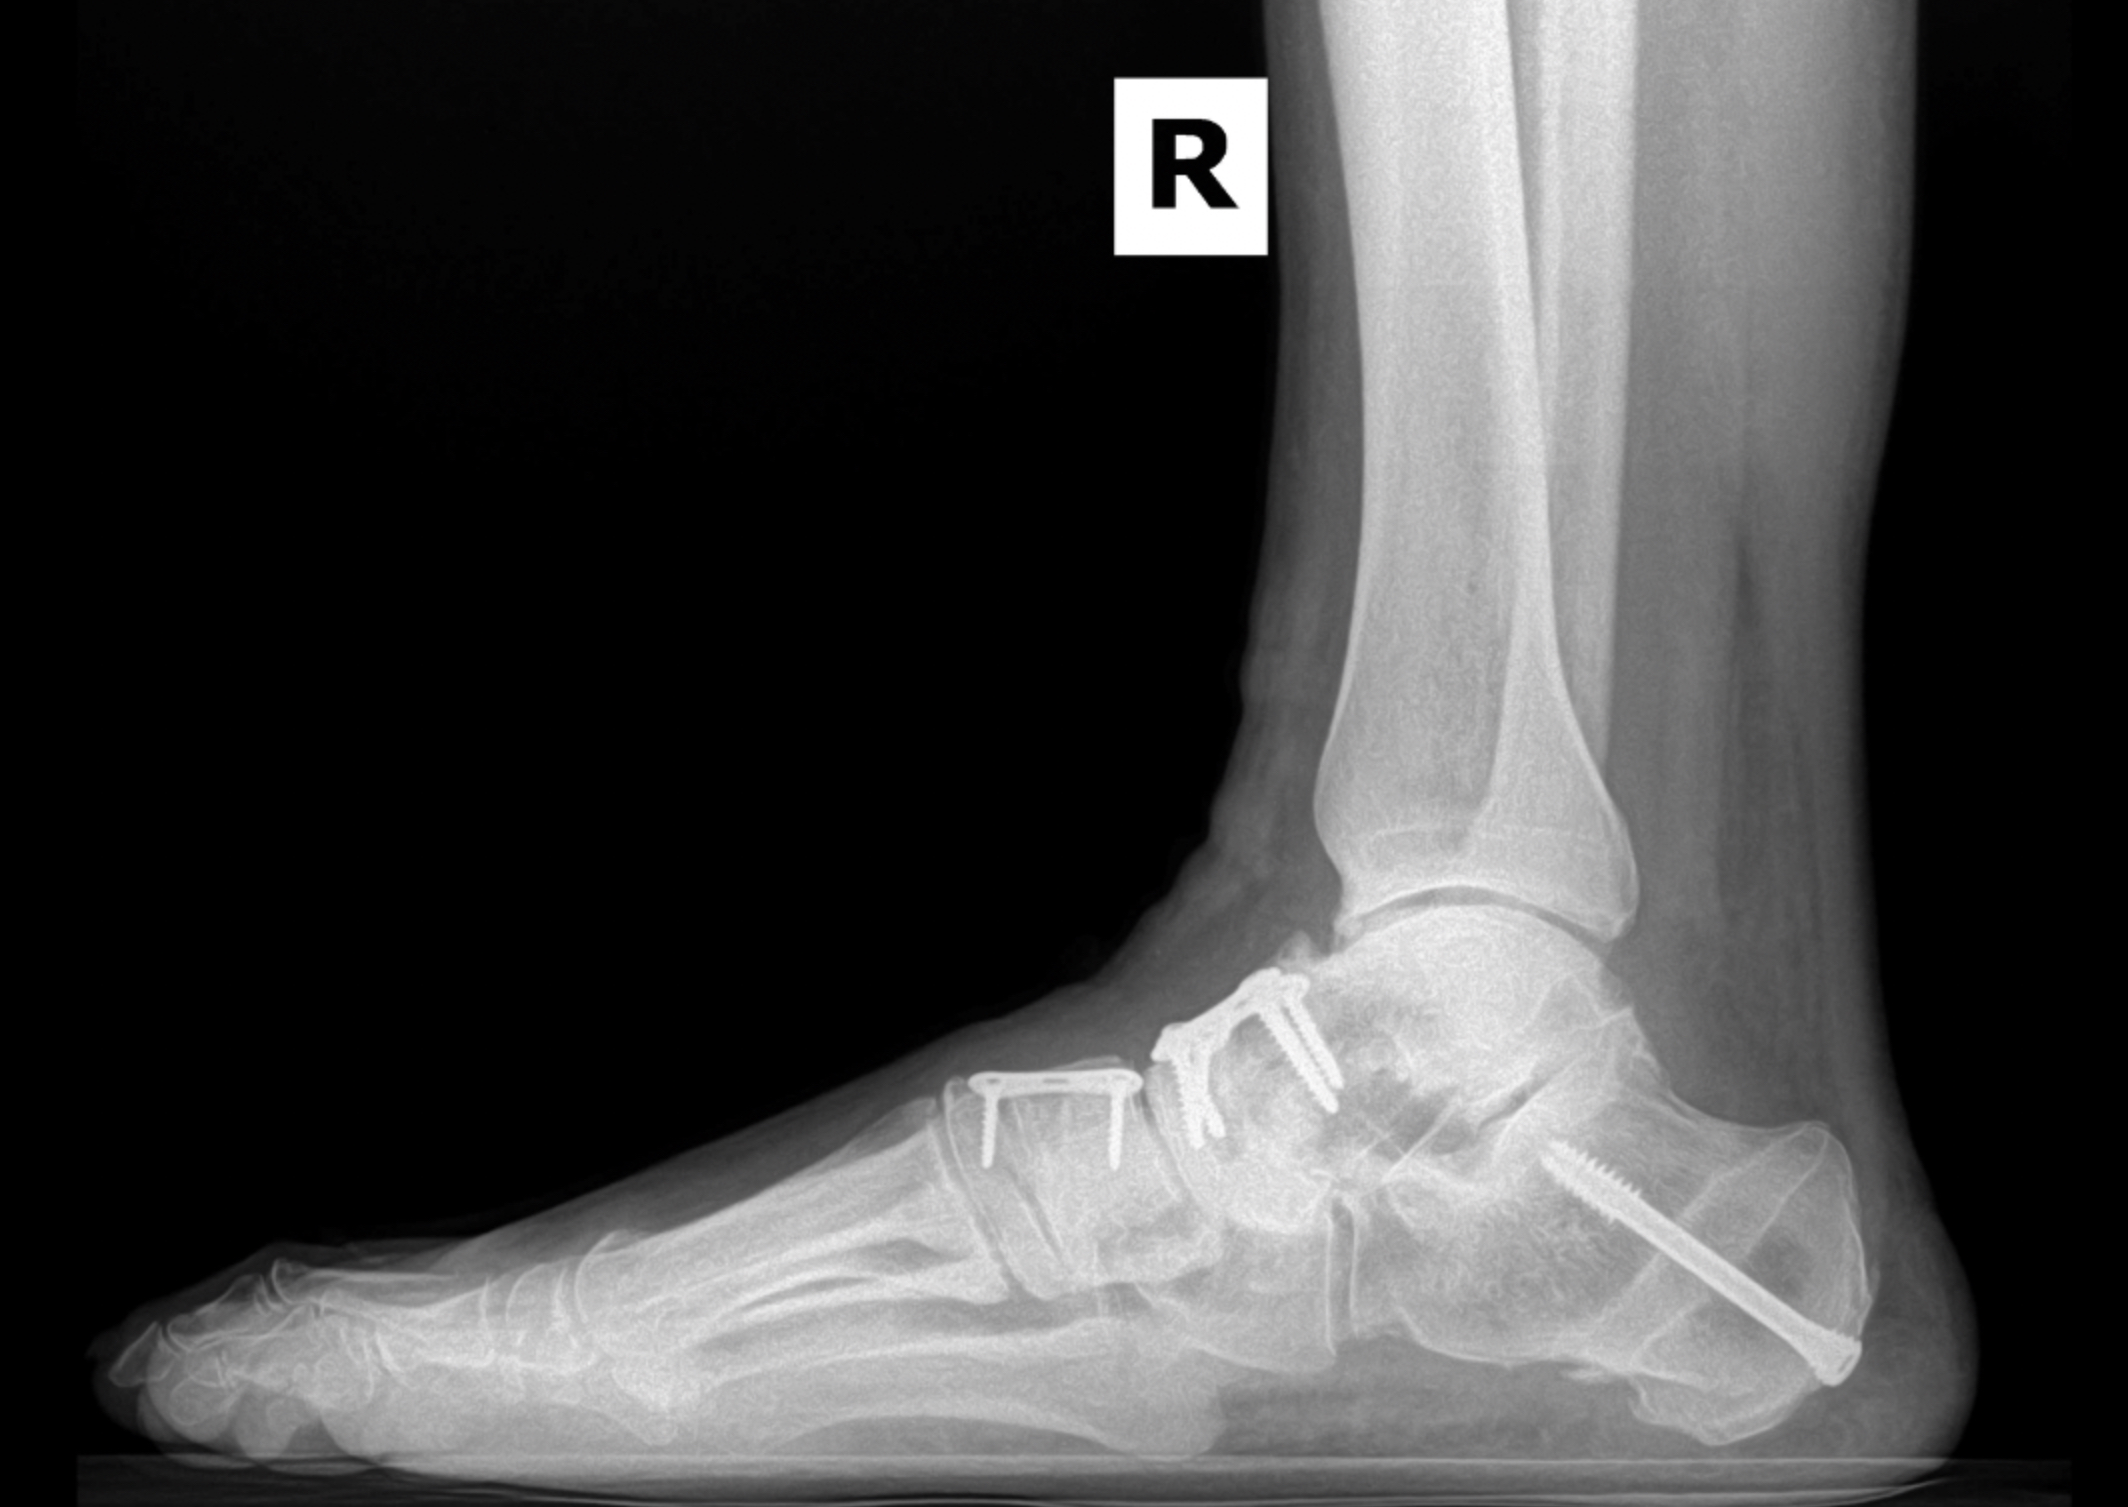

Arthritic flatfoot

Postop XR Images